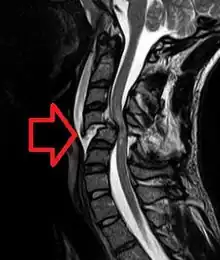

| MRI of a fractured and dislocated cervical vertebra (C4) in the neck that is compressing the spinal cord | |